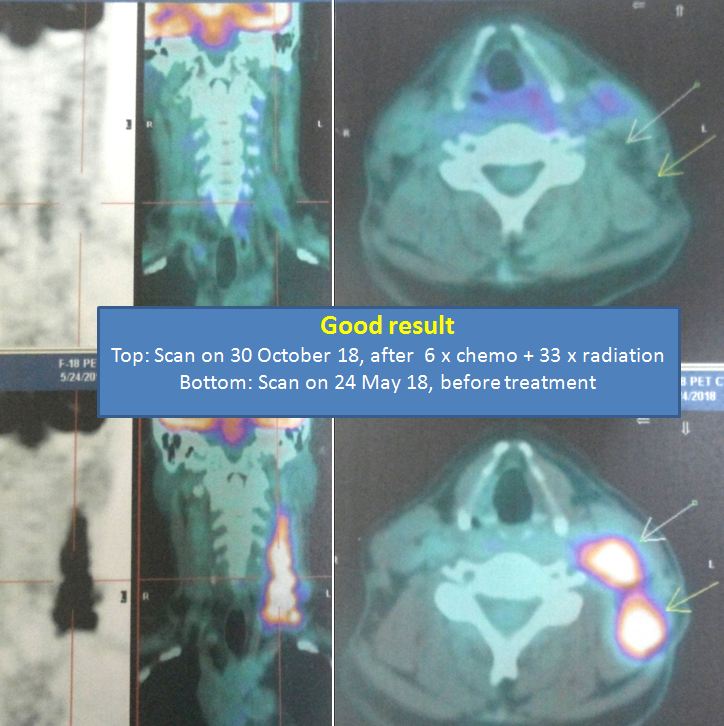

A repeat PET scan was done seven months later. Is the cancer gone or is he getting worse?

Study the three pictures below and compare them with the PET scan done on 10 August 2017 (above). You don’t need to be a doctor to know that PK is not getter better. He is getting worse and the cancer has spread more widely.

The PET scan report of 11 April 2018 stated the following:

- New development of large reticulonodular changes at the left upper lobe, probably related to post-radiation inflammation.

- New FDG avid mediastinal nodes, probably reactive nodes from inflammation.

- Metabolic increment in the left level IV cervical node.

- Mixed metabolic changes in the retroperitoneal and pelvic nodes.

- New development seen at thoracic stomach wall nodule and peri-bowel node at celiac axis, and celiac trunk nodes.